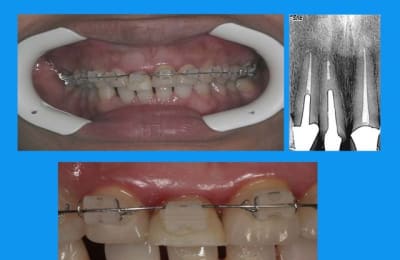

l'odf a utilisé un arc 0.014 thermique ,force constante faible

la dent provisoire a été meulée au fur et à mesure de la traction = 3mm

elle a un sourire très gingival et des prothèses déjà en place:la chir de 3 à 3 aurait été plus rapide mais peut être moins esthetique... et je n'ai pas osé....

Tu n'as donc pas nivellé la ligne des collets ?

n'ayant pas ton coup de bistouri,j'ai reculé,mis en attente et prié...

la fracture était basse en vestibulaire,la gencive assez fine et je n'ai pas "senti" le remodelage gingival sur la provisoire(qu'en termes corrects ma peur de rater peut être exprimée:)

d'où l'empreinte avec bague de Cu pr aller chercher les limites

autre question:"les incisives du bas"

la patiente a entamé son traitement odf pr une demande esthetique(marre des diastème)

pr des raisons fonctionnelles aussi,cela ns paraissait une bonne idée

elle a une microdontie relative de ces insicives qui st maintenant redressées, alignées avec des diastèmes equidistants

et maintenant....

que feriez vous?

on comprend mieux la microdontie relative

les diastemes te genent? tu as peur de la recidive apres l'ortho?